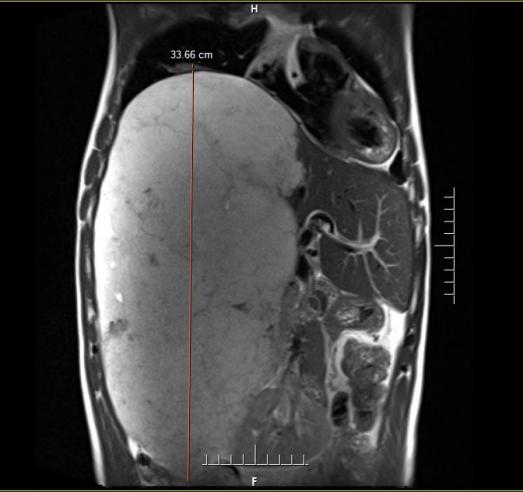

近日,李先生因上腹持续不适前往中国科大附一院就诊。影像学检查结果让他和家人震惊不已——腹腔里竟然长了一个巨大的占位性病灶,纵向直径约 34 厘米,从上腹一直延伸至盆腔,如同怀胎十月的胎儿般占据了腹腔大量空间,最终确诊为“肝脏巨大占位(肝血管瘤可能)”。

“如此巨大的肝血管瘤在临床上极为罕见。”接诊的中国科大附一院副院长、普外科肝胆外科主任医师尹大龙介绍,更危险的是它紧贴重要血管以及肝脏胆道等器官组织,甚至将右侧肾脏挤压到了左侧。

术前MRI提示肝脏巨大占位,纵向直径约34cm,直抵盆腔